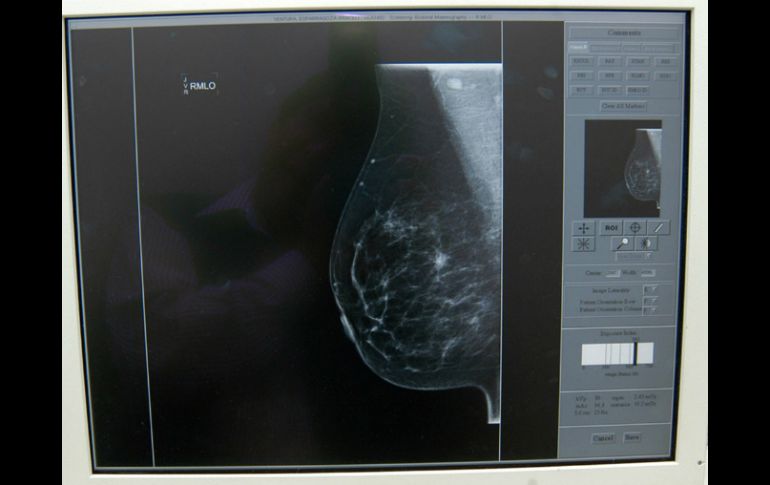

Tecnología | Es reservada a mujeres con diagnóstico de alteraciones genéticas Mastectomía alternativa para prevenir cáncer de mama Es reservada a mujeres con diagnóstico de alteraciones genéticas que conducirán al desarrollo de esta enfermedad Por: NTX 25 de junio de 2013 - 15:16 hs La mastectomía subdérmica consiste en la extirpación del tejido glandular de la mama, preservando el complejo areola-pezón. ARCHIVO / GUADALAJARA, JALISCO (25/JUN/2013).- La mastectomía dubdérmica podría ser una alternativa preventiva reservada a mujeres con diagnóstico de alteraciones genéticas que invariablemente conducirán al desarrollo de cáncer de mama, afirmó el experto Juan Manuel Castro Cervantes. El especialista del Instituto Mexicano del Seguro Social (IMSS) en Jalisco señaló que aún cuando la autoexploración y estudios como ecografías y mastografías posibilitan la detección temprana del cáncer de mama, existen alternativas profilácitcas (preventivas) como la mastectomía subdérmica. Castro Cervantes, titular del departamento de oncocirugía en el Hospital de Especialidades del IMSS, detalló que la mastectomía subdérmica consiste en la extirpación del tejido glandular de la mama, preservando el complejo areola-pezón para la posterior colocación de implantes. Explicó que esta alternativa se reserva a mujeres con antecedentes de la enfermedad en línea directa, es decir madre o hermanas, y más para aquellas con alteraciones en los genes BRCA 1 y BRCA 2, que en condiciones normales regulan el ciclo celular y evitan su proliferación desordenada y que en estas pacientes están dañados. Indicó que en el servicio a su cargo, del total de pacientes con diagnóstico de cáncer de mama, un 30 por ciento tiene antecedente familiar y del cinco al 10 por ciento presenta la alteración genética referida en el párrafo anterior y por lo mismo "es cuando realmente pueden tener un problema hereditario serio". Para considerarse preventiva, la mastectomía subdérmica debe hacerse antes de que la glándula haya desarrollado cáncer, "en los pacientes con antecedentes familiares directos, mamá o hermanas que hayan tenido enfermedad maligna de mama", dijo. Aconsejó un asesoramiento genético para que de ahí se pueda derivar al estudio de determinación de BRCA 1 o 2, estrechamente relacionados a cáncer de mama y de ovario. Señaló que aunque se preserva el complejo areola-pezón, se trata de una cirugía radical cuya efectividad máxima es del 90 por ciento. "Siempre queda tejido (porque) la cirugía abarca el reborde mamario pero existe una extensión de tejido a la axila y ese es el riesgo, o bien algunos tejidos microscópicos que pudieran quedar y que en un momento, dada la predisposición de la paciente pudieran desarrollar la enfermedad", apuntó. Reiteró que de ahí que el máximo beneficio de la mastectomía subdérmica se establezca en un 90 por ciento. Destacó que toda mujer posterior a una mastectomía subdérmica debe continuar con revisiones médicas periódicas "cada seis meses o cada año, en función de la intensidad del riesgo y esto significa la realización de ecosonogramas y mamografías". Agregó que el hecho de que estas pacientes tengan implantes en sustitución de las glándulas que le fueron retiradas, no representa problemas a la hora del estudio imagenológico o ecosonográfico de la mama. Existen técnicas radiológicas que con tomas desde diferentes ángulos pueden captar tejido residual, lo importante es que estas pacientes no se descuiden, enfatizó el especialista. Y su aseveración tiene sustento ya que al servicio a su cargo, de las 207 cirugías por cáncer de mama hechas de enero a noviembre del año pasado, 47 fueron conservadoras (cuadrantectomía) y 160 radicales. Temas IMSS Ciencia médica Cáncer de mama Lee También Julieta Fierro será homenajeada en la FIL INAPAM: ¿Cómo solicitar un turno para consulta médica gratuita? La creación de empleo va en caída este año Genera Jalisco 9 mil 345 empleos formales en septiembre Recibe las últimas noticias en tu e-mail Todo lo que necesitas saber para comenzar tu día Registrarse implica aceptar los Términos y Condiciones